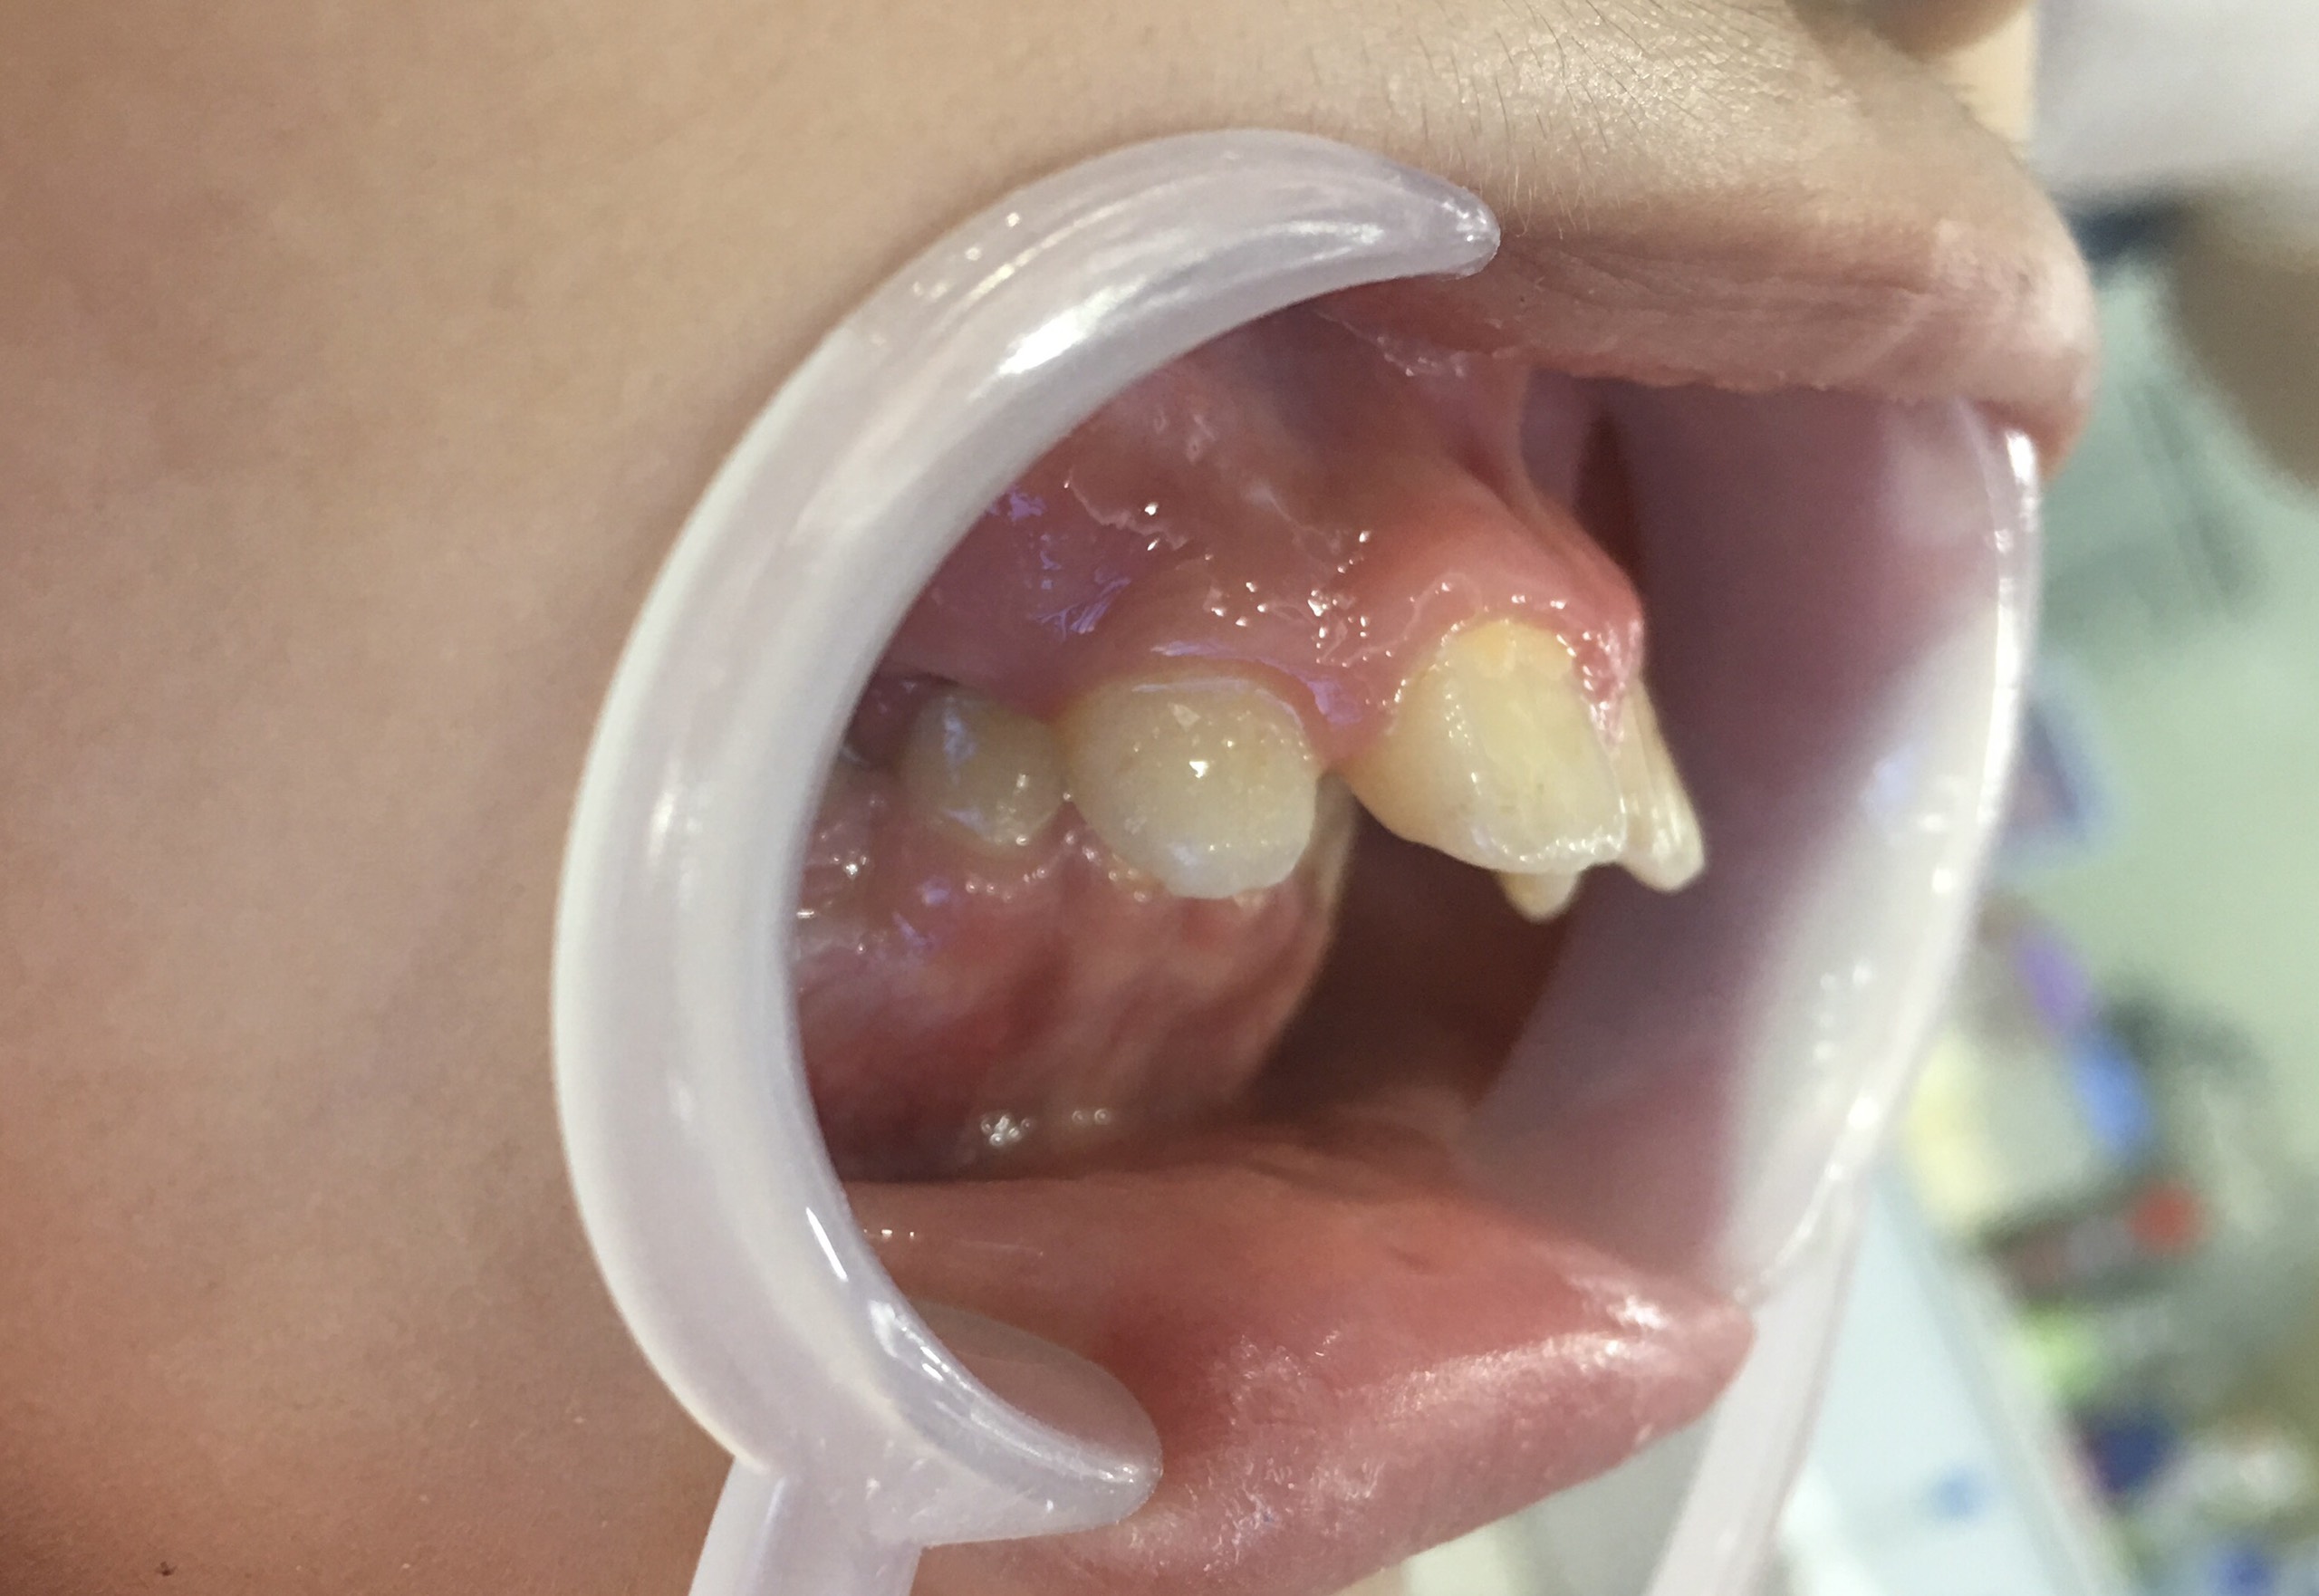

Răng dính khớp và những biến chứng không rõ nguyên nhân

Răng dính khớp là một trong những rào cản lớn nhất của chỉnh nha. Do đó, khách hàng có răng dính khớp cũng thuộc nhóm những người không nên niềng răng.

Chân răng dính trực tiếp vào xương hàm làm mất đi khoảng dây chằng nha chu – "lớp đệm" cần thiết để răng có thể dịch chuyển. Tình trạng này thường xuất hiện ở những bệnh nhân từng có tiền sử chấn thương vùng hàm mặt hoặc do yếu tố di truyền. Số liệu thực tế cho thấy có khoảng 0,5% trường hợp răng đang trong quá trình niềng thì đột ngột dính khớp không rõ nguyên nhân, khiến răng trở nên "cứng đầu" hơn cả một trụ Implant và không hề nhúc nhích dù bác sĩ tăng lực kéo.

Răng dính khớp là một trong những rào cản lớn nhất của chỉnh nha

Việc cố gắng dùng lực mạnh sẽ gây ra phản lực làm xô lệch các răng khỏe mạnh xung quanh và gây đau nhức dữ dội. Bác sĩ có thể bắt buộc phải nhổ bỏ chiếc răng dính khớp đó và thay thế bằng một trụ Implant để đảm bảo tính thẩm mỹ và khớp cắn chuẩn cho toàn hàm.